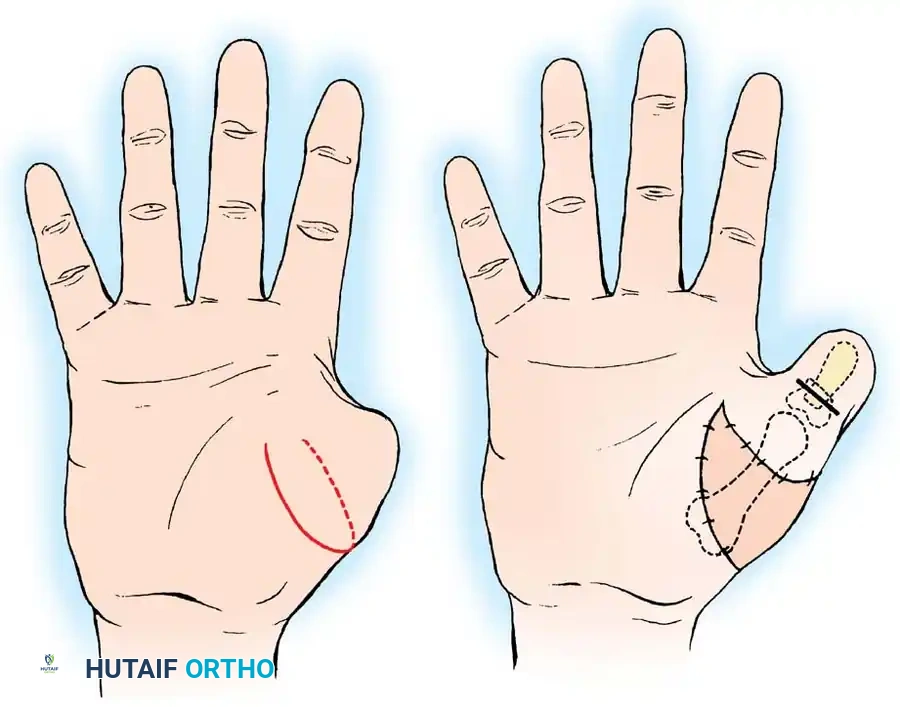

- Incision: Make a curved, horseshoe-shaped incision around the dorsal, radial, and volar aspects of the base of the thumb.

- Flap Elevation: Undermine the skin distally, staying strictly superficial to the main venous drainage network to prevent venous congestion and subsequent flap necrosis. Continue undermining until a hollow, thimble-like flap has been elevated and slipped off the end of the bony stump. The blood supply to this flap is maintained via the arborization of vessels around the base of the index finger in the thumb web.